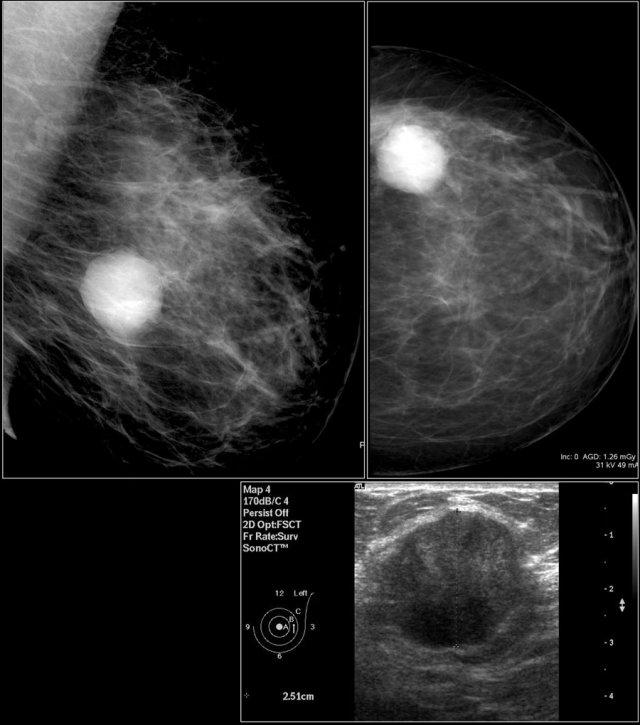

Bệnh nhân này nhập viện vì có khối u ở vú trái.

Tuy nhiên, ở vú phải phát hiện một nhóm vôi hóa dạng vô định hình và đa hình thái nhỏ.

Siêu âm được thực hiện để đánh giá thêm.

Siêu âm vùng này phát hiện một khối bờ không đều, được xác nhận là ung thư biểu mô tuyến qua chọc hút tế bào bằng kim nhỏ (FNA).

Để xác định liệu khối có nằm trong vùng vôi hóa hay không, thuốc cản quang được tiêm vào trong khối.

Rõ ràng khối nằm ở một vùng khác của tuyến vú.

Lúc này cần tiến hành sinh thiết hút chân không đối với vùng vôi hóa, vì có thể chúng ta đang đối mặt với ung thư biểu mô ống tuyến vú tại chỗ (DCIS) ở một vùng và ung thư biểu mô xâm lấn ở một vùng khác.